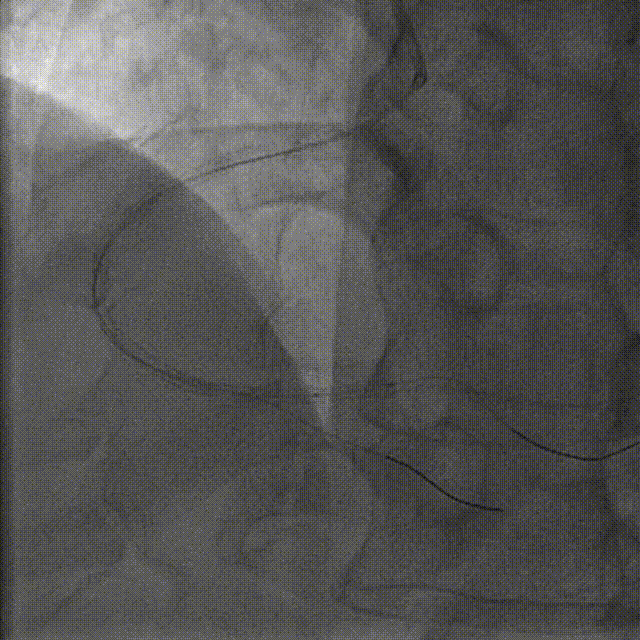

在Telescope™导引延长导管辅助下,于远段至中段病变串联植入支架2.5*38mm、2.5*38mm

在Telescope™导引延长导管辅助下,于右冠脉中段至近段串联植入支架3.0*29mm、3.0*18mm